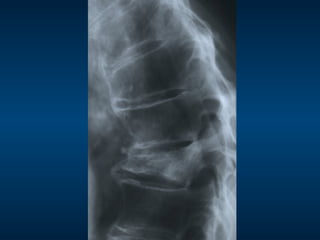

•  85 year old female

•  Severe acute on chronic mechanical

back pain

– Can’t sleep

– Limited walking to only a few steps

•  Spontaneous onset

•  No known trauma

Radiograph (X-ray)

24/3/2012

24/3/2012 16/12/2011